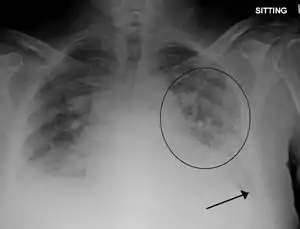

| Pulmonary edema with small pleural effusions on both sides | |

Low oxygen saturation in blood and disturbed arterial blood gas readings support the proposed diagnosis by suggesting a pulmonary shunt. A chest X-ray will show fluid in the alveolar walls, Kerley B lines, increased vascular shadowing in a classical batwing peri-hilum pattern, upper lobe diversion (biased blood flow to the superior parts instead of inferior parts of the lung), and possibly pleural effusions. In contrast, patchy alveolar infiltrates are more typically associated with noncardiogenic edema[2]